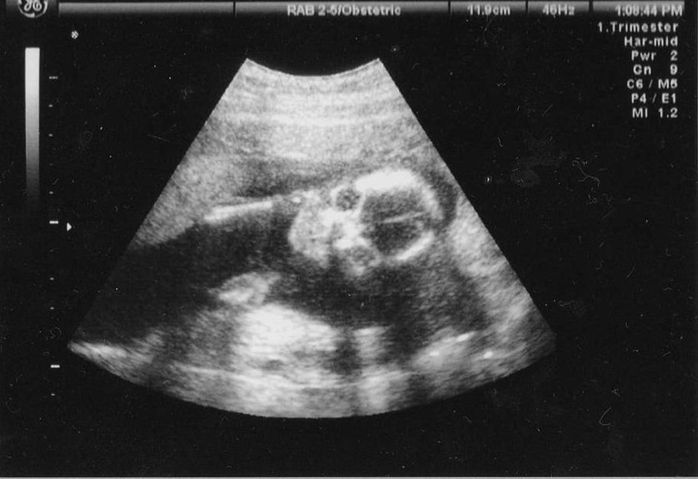

妊娠13週目のエコー写真

頭の大きさと体長から体重を割り出しています。